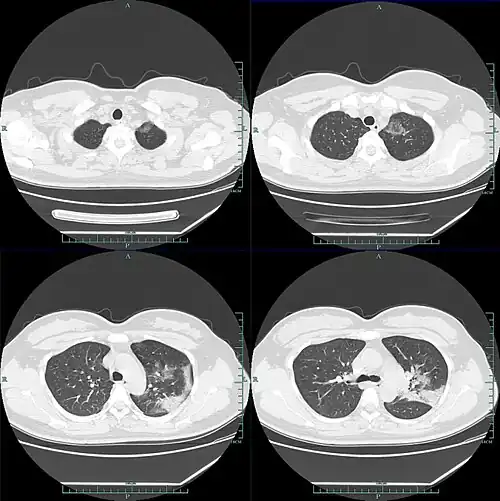

W badaniu 1099 chińskich pacjentów za pomocą tomografii komputerowej stwierdzono zmiany w płucach typu mlecznej szyby w 56% przypadków. Zmian w badaniu radiologicznym nie wykazano u 17,9% pacjentów z łagodną postacią choroby oraz u 2,9% pacjentów z ciężką postacią choroby. Limfopenia była obecna u 83,2% przyjętych pacjentów. 5% pacjentów zostało przyjętych na oddziały intensywnej terapii, 2,3% wymagało mechanicznego wspomagania wentylacji płuc, a 1,4% zmarło[39]. Według zespołu badawczego Bernheima obustronne i obwodowe zacienienia w płucach typu mlecznej szyby są najczęstszymi objawami widocznymi na skanach tomografii komputerowej. Konsolidacje miąższu płucnego, liniowe zacienienia płuc oraz objaw odwróconego halo to inne typowe symptomy widoczne w obrazowaniu radiologicznym. Początkowo zmiany są widoczne w jednym płucu, jednak – wraz z rozwojem choroby – u 88% pacjentów stają się obecne w obu płucach[40]. Dzieci zdają się przechodzić chorobę lepiej niż dorośli i występują u nich łagodniejsze objawy, jednak brakuje wciąż danych, aby stwierdzić to jednoznacznie[41].

Zmiany w diagnostyce obrazowej u pacjentów obejmują najczęściej[47][50][55]:

- obustronne i obwodowe zacienienia w płucach typu „mlecznej szyby”

- niejednolite konsolidacje miąższu płucnego

- liniowe zacienienia w płucach

- objawy odwróconego halo

- predylekcję do występowania zmian w tylnych segmentach lub płatach dolnych